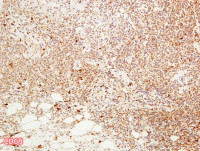

左颊黏膜肿物

性别

女

年龄

63岁

发现左颊黏膜肿物半个月,无明显疼痛

肿物1.5*1.5*1cm,界清,切面实性,红褐色,质软

图2